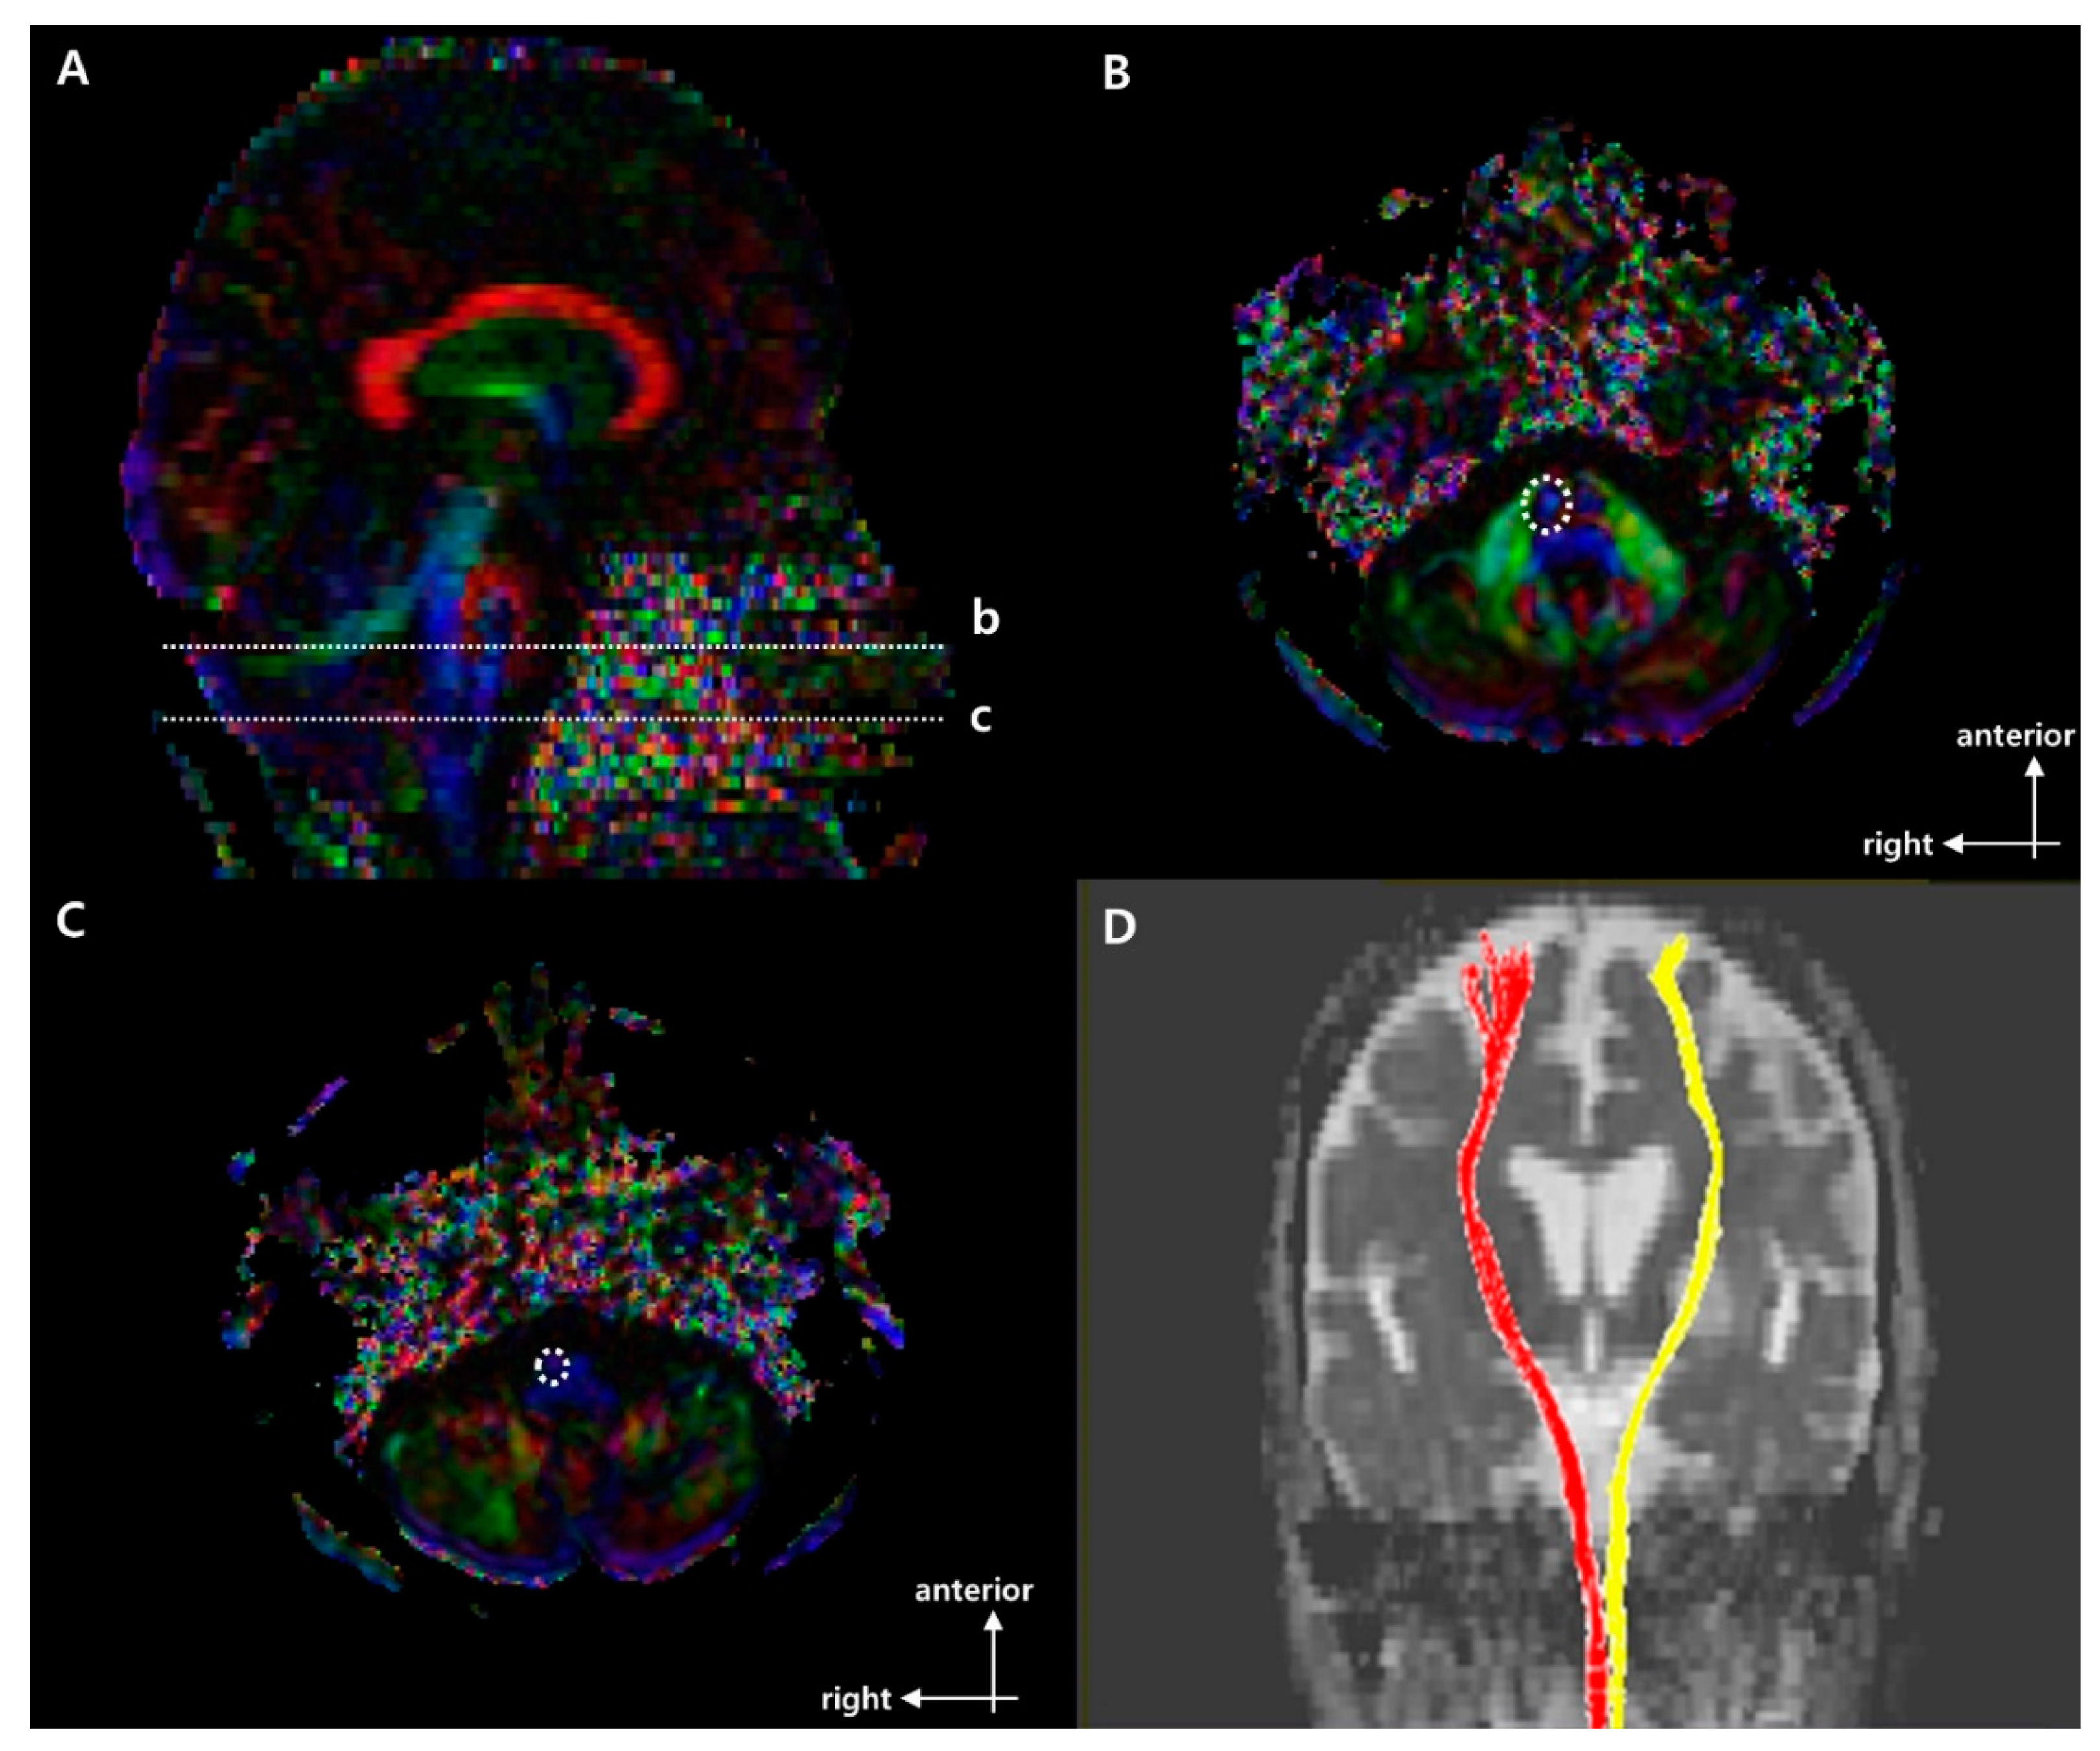

2.3. Fiber Bundle Tracking